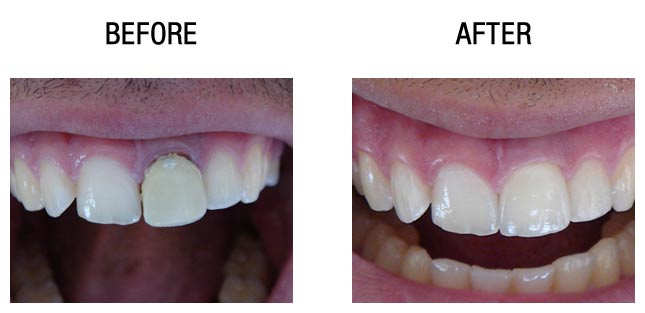

牙齿种植前后对比

牙齿种植前后对比